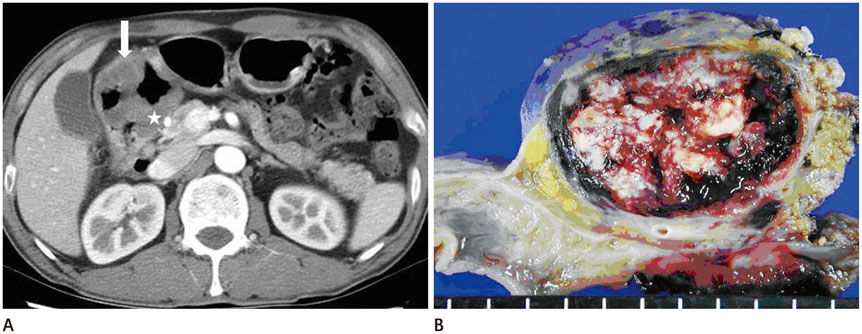

Duodenal Metastasis of Pulmonary Pleomorphic Carcinoma: A Case Report

- Pulmonary pleomorphic carcinoma is an uncommon malignant lesion of the lung. A chest radiograph of 53-year-old man who was suffering from a cough revealed a well-defined mass-like opacity with a broad base on the pleura at the apico-posterior segment of the right upper lobe of the lung. The subsequent chest computed tomography (CT) scan demonstrated an inhomogeneous enhancing mass with central low-attenuation in the right upper lobe. A lobectomy was performed and the mass was determined to be a pleomorphic carcinoma with visceral pleura invasion. Forty days after the operation, the patient complained of melena and an abdominal CT revealed an intraluminal and extraluminal protruding mass around the prepyloric antrum and duodenal bulb. The mass was removed by en-block surgery and diagnosed as metastatic pleomorphic carcinoma from the lung. Previous articles reported a median survival time of 3-10 months for pleomorphic carcinoma, but in this case, the patient has continued to survive, 11 years after surgery. Chest and abdominal CTs have revealed no evidence of tumor recurrence or metastasis.